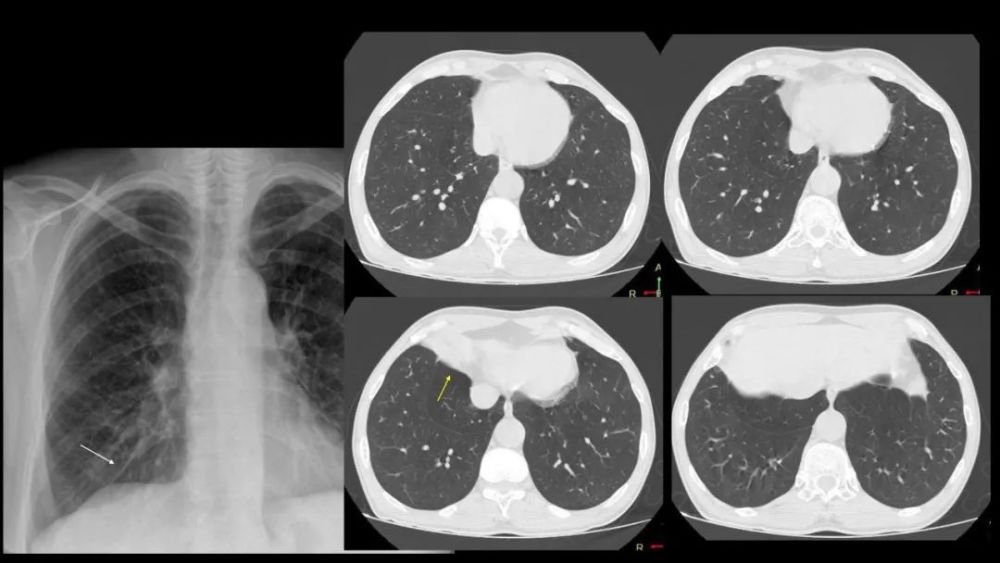

奇 裂

奇静脉分隔右肺上叶尖段

不是真正的附叶 , 因为没有自己的支气管 解剖标本的发生率为1% , M:F=2:1

X:细线状隆起(相对于纵膈) , 穿过右肺尖 , 前位上纵膈胸片可?气体

CT: 奇裂从SVC和气管后穿过